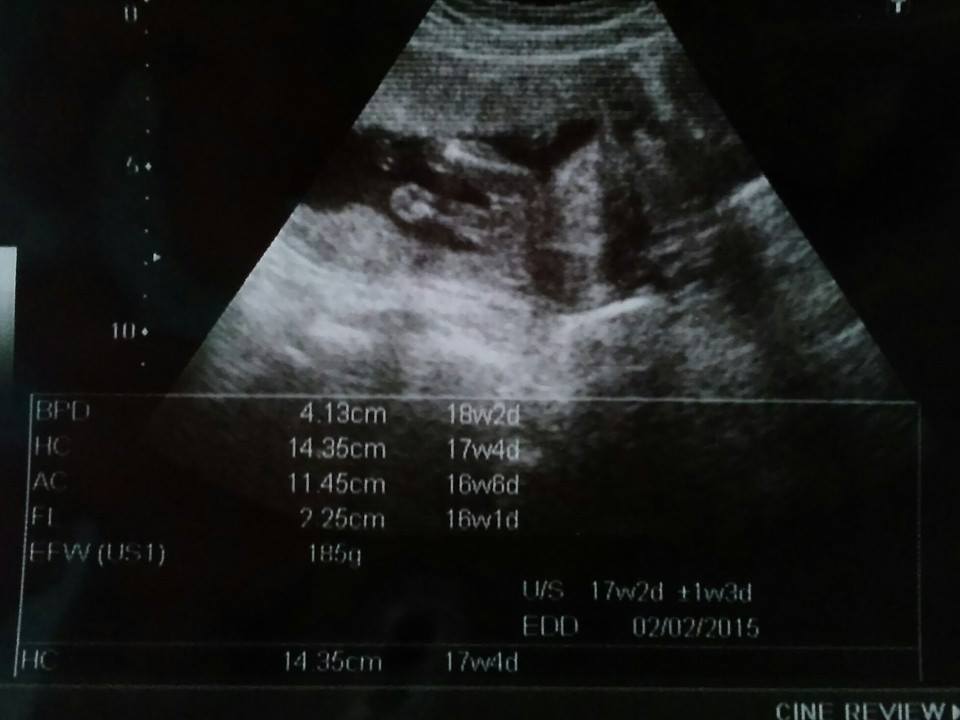

อัลตร้าซาวน์แบบนี้ ชายหรือหญิงคะ

อัลตร้าซาวน์ ออกมาแบบนี้ พอจะดูออกมั้ยคะว่า ชายหรือหญิง